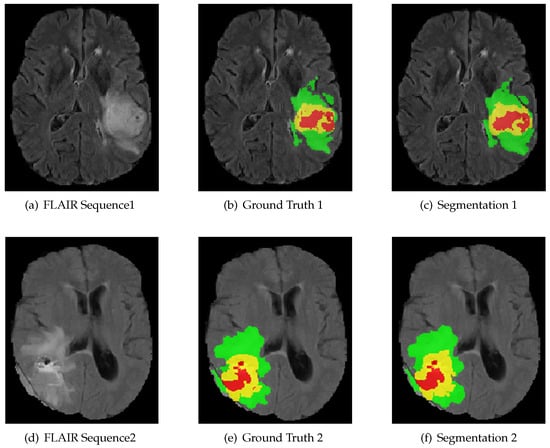

We evaluate our algorithm on the BraTS 2018 challenge dataset against the state-of-the-art methods. We introduce the dataset as follows. The multi-modal 3D MRIs are provided by the BraTS 2018 challenge [3,28,29]. The training data consist of 75 low grade and 210 high grade gliomas. Each subject has FLAIR, T1, T1C and T2 MRI scans, and even ground truth (GT) obtained by hand segmentation from experts. The multi-modal 3D MRIs originated from 19 institutions and employed different protocols, magnetic field strengths and MRI scanners [30]. Annotations include 4 tumor subregions: the normal tissue (label 0), necrotic and non-enhancing tumor (label 1), peritumoral edema (label 2) and active/enhancing tumor (label 4). The annotations are combined into 3 nested subregions. WT, TC and ET refer to the regions of whole tumor (label1, label2, label4), tumor core (label1, label4) and enhancing tumor (label4), respectively, as shown in Figure 4.

Figure 4.

MRI image modality sequence along with ground truth. The whole tumor (WT) class indicates all visible labels (a combination of green, yellow and red labels), the tumor core (TC) class is a combination of red and yellow, and the enhancing tumor core (ET) class is shown in yellow. The green region indicates peritumoral edema, the yellow region indicates active/enhancing tumor and the red region indicates necrotic and non-enhancing tumor. These are the slices from the axial plane.